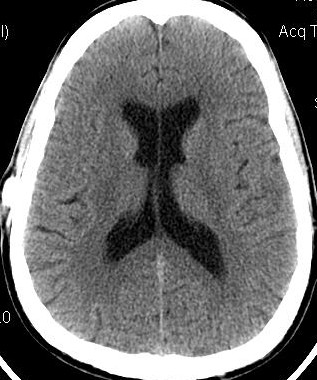

Below, are my CT images beginning on Jan. 17, 2011, where there is enlargement of the ventricles, followed by further enlargement on April 9, 2011, and what appears to be more enlargement on June 8, 2011, despite my May 23, 2011 revision. Then, there appears to be a slight decrease in ventricular enlargement on June 20, 2011, followed by normal size (almost too small) ventricles on July 23, 2011. We felt my ventricles came down in size too quickly, and began to raise the proGav setting over a period of two months, eventually up to 6, and rescanned me on Sept. 15, 2011. Those results indicated my ventricular enlargement had returned, so the proGav was returned to a lower setting of 2.

Under my CT images below, I list each of the proGAV's corresponding settings. It was initially set at 10 during surgery, with no improvement in complaints after one week, I asked that it be lowered to 7, and one week later to 5, then to 3, and finally to 0. During this period, almost every morning I awoke with a substantial headache that I assumed was due to increased ICP and underdrainage. On the June 20, 2011, CT we could finally see some decrease in the dilation of my ventricles, and determined the shunt to be working. But, we were still puzzled by the ongoing awaking a.m. headaches. For this reason, it was temporarily raised to a setting of 2, and then with no relief back down to 0. It remained at 0 for almost a month when the July 23, 2011 scan revealed normal sized ventricles.  Because of the relatively short period it took for my ventricles to come back to normal, we raised the proGAV gradually to 6, and back down to 2 after the Sept. 15, 2011 scan showed a return of ventriculomegaly.

June 8, 2011 proGAV  5/20    June 20, 2011 proGAV 3/20      July 23, 2011 proGAV 0/20    Sept. 15, 2011 proGav 6/20   Feb. 1, 2012 proGav 0/20